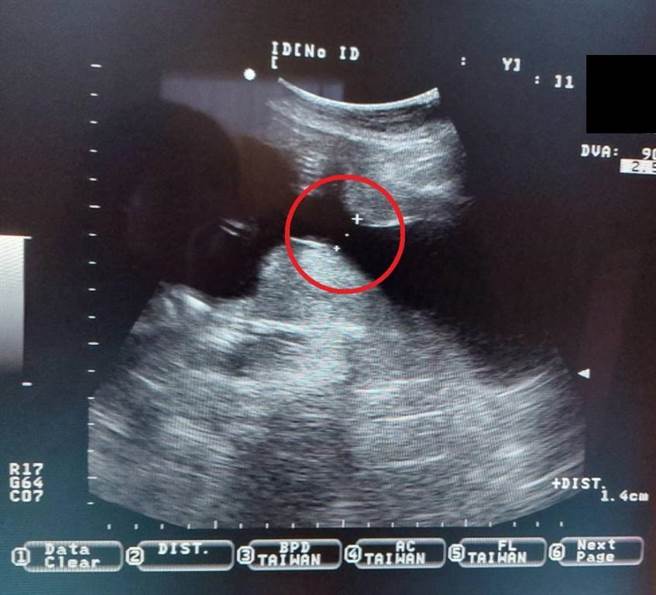

大千綜合醫院醫療副院長暨婦產科醫師林敬旺表示,子宮頸就像是子宮的出口,懷孕還未足月前,子宮頸的長度至少有3公分,一般到懷孕足月時,子宮頸會軟化成熟、變短、擴張來為生產做準備;而子宮頸閉鎖不全則是在未足月前,子宮頸的長度就已短於2.5公分,此時則可能有發生早產的風險。

林醫師說,子宮頸閉鎖不全的高風險族群包含過去曾在懷孕中期流產、或接受過子宮頸手術的病史,針對高風險的孕婦可考慮在懷孕20周前接受預防性的子宮頸環紮手術,來避免發生早產。然而有部分的子宮頸閉鎖不全的孕婦是沒有病史或症狀,如同賴媽媽一樣,因此定期於產檢時量測子宮頸長度非常重要。